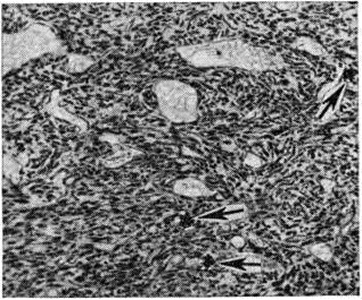

Рис. 1.

Микроскопическая картина дифференцированной гемангиоперицитомы: сосуды капиллярного типа (1), окружённые веретенообразными клетками (2).

Дифференцированная Гемангиоперицитома встречается редко, может возникать в любом возрасте, часто у детей. Как правило, характеризуется медленным ростом, обычно достигает крупных размеров, сохраняя при этом чёткие контуры и подвижность. Локализуется преимущественно в коже, мягких тканях туловища и конечностей, реже — в забрюшинном пространстве, средостении, сальнике, языке и внутренних органах (печень, кишечник, мозг и другие.). Макроскопическое строение — опухоль узловатой формы, на разрезе розовато-красного цвета, пористого строения, с обилием подходящих к ней сосудов. Микроскопически характеризуется большим количеством капилляров, выстланных эндотелием и окружённых округлыми, овальными или веретенообразными клетками с темными ядрами и светлой цитоплазмой (рисунок 1). Клетки оплетены густой сетью аргирофильных волокон. Основным отличием Гемангиоперицитома от капиллярной ангиомы является массивная пролиферация периваскулярных клеток, которые большинство исследователей относит к перицитам.